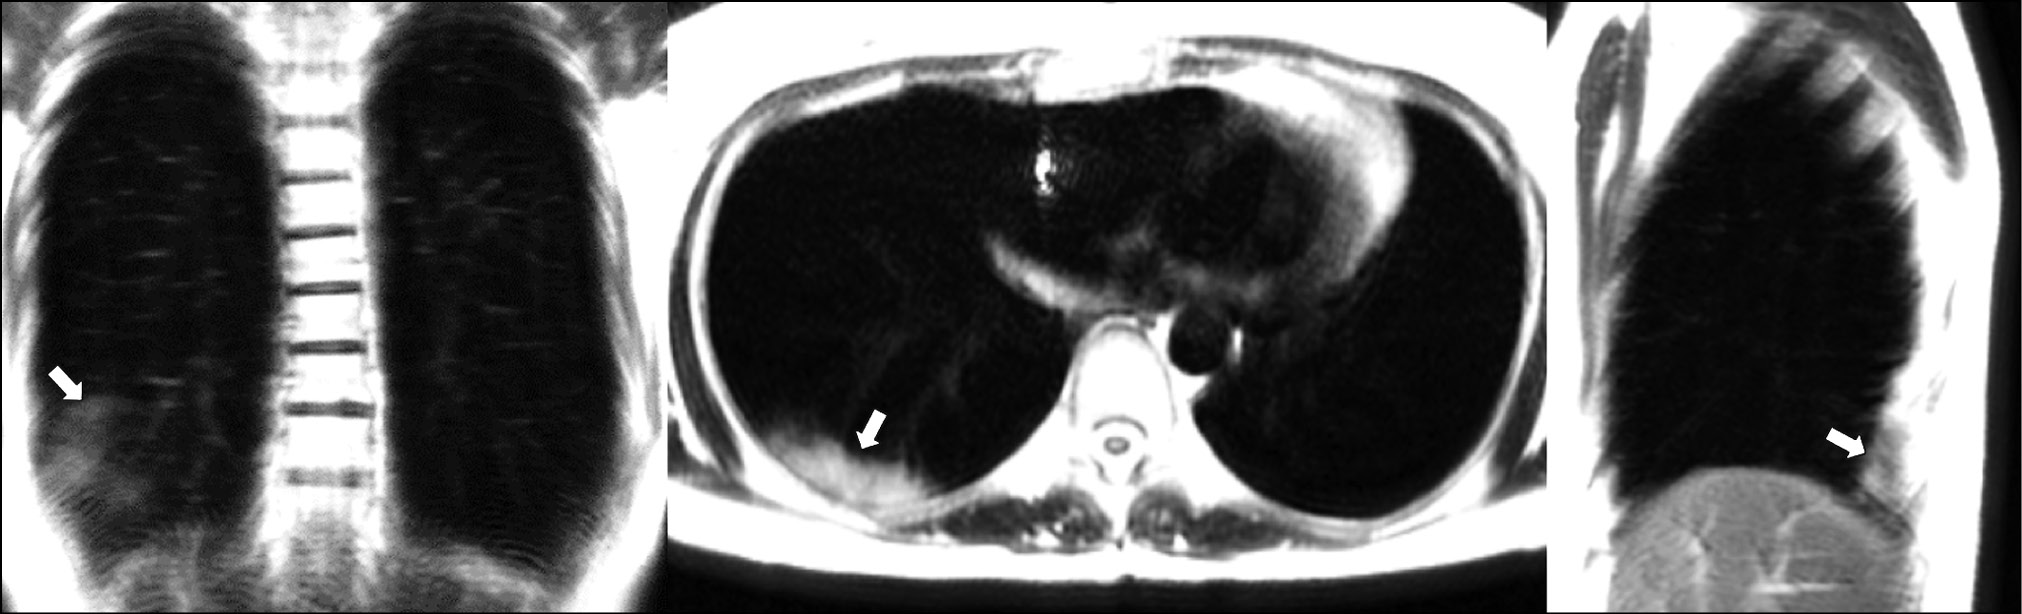

A patient (female, 25 years old) complained of a dry cough, high fever (up to 39°С), chills, and chest heaviness. She went to the hospital on the sixth day after the onset of the first symptoms, when they became extremely pronounced. Dynamic MRI showed a large area of increased signal in segments S6, S8, and S9 of the left lung’s lower lobe. An inhomogeneous increased signal was found during inhalation in the coronal, axial, and sagittal planes (Fig. 3). The signal intensity increased in the coronal and sagittal planes during exhalation (Fig. 4), with the increased visual size of the affected areas and the expanded “cloudy sky” area. These findings may be attributed to expiratory contraction of lung tissue during exhalation.

Figure 3. Dynamic magnetic resonance imaging of the lungs during inhalation in the coronal, axial, and sagittal planes. Orange arrows point to consolidation areas visible during inhalation (S6, S8, and S9). The white arrow points to the area with the “cloudy sky.”

Chest breathing movements can also influence scanning and thus the observed pattern. The “cloudy sky” observed at the periphery of the signal enhancement area during inhalation becomes more intense during exhalation, most likely due to increasing density of the lung parenchyma.